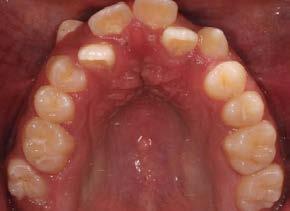

Paciente de 14 años y 8 meses, moti vo de consulta: “mi mordida no me gusta” el patrón esquelético es cla se II, hiperdivergente, clase II molar derecha y clase I molar izquierda, los caninos superiores en infraoclusión overbite disminuido, apiñamiento severo superior, moderado inferior, con los dientes 12 y 22 palatinizados, el 13 ectópico, con mordida abierta anterior, y las líneas medias desvia das.

hacia la derecha y la línea media dental inferior a la izquierda, con mordida abierta anterior, el canino superior derecho se encuentra fuera del arco ( Figura 3 ), en la oclusal superior los inci sivos laterales palatini zados y paladar ojival profundo, en la lateral derecha una relación molar clase II y relación canina no determinable (Figura 4), en la izquier da una relación molar clase I y relación canina no deter minada.